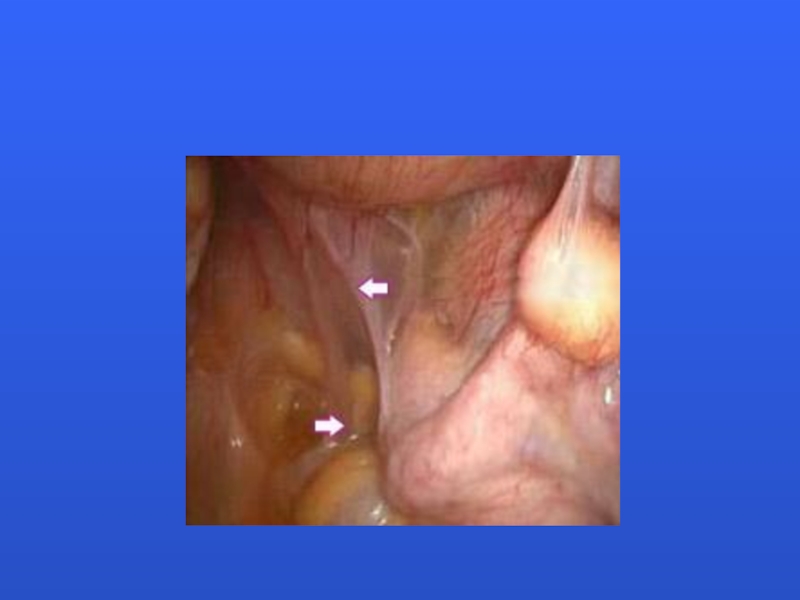

Слайд 31Surgical treatment

Слайд 42Surgical treatment